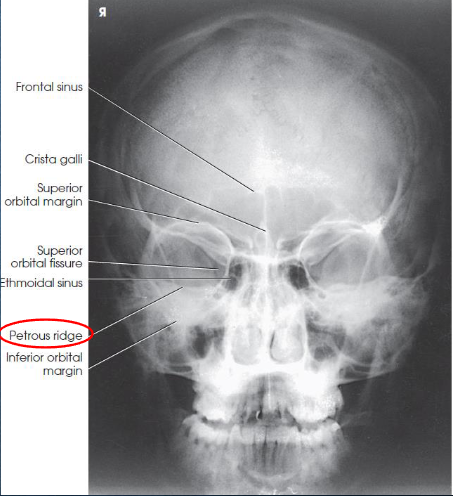

PA axial (Caldwell) facial bones

PA axial (Caldwell) facial bones image criteria

shows:

orbital rims

maxillae

nasal septum

zygomatic bones

anterior nasal spine

petrous ridges in lower third of orbits (caused be 15 degree caudal angle)

entire orbits and facial bones

no rotation or tilt:

equal distances from lateral borders of skull and lateral borders of orbits

MSP of head alligned with long axis of collimated field

symmetric petrous ridges